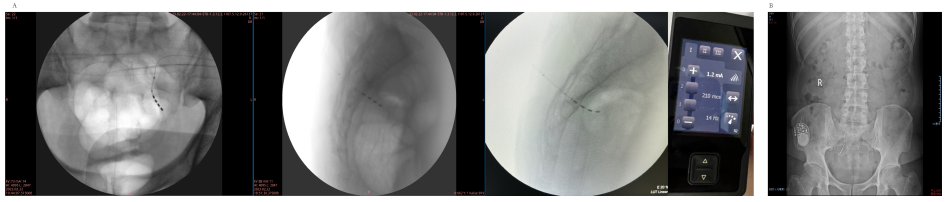

2023年2月22日,患者在局麻下进行电极植入术,刺激参数为1.2mA,210μs,14Hz,0-3+。测试治疗期间,患者的夜间遗尿症状消失,夜尿次数减少,泌尿系症状明显改善。2023年3月8日,患者进行了骶神经刺激器植入术,术后彩超显示,尿量变化不大,但残余尿明显减少。2023年11月门诊随访,患者无夜间遗尿或夜间排尿减少,排尿时间明显缩短,NBSS评分显著改善。彩超显示双侧无肾积水,无输尿管扩张,残余尿约10ml,患者的头痛、头晕发作频率减少。尿动力学评估与压力-流速同步测量显示,膀胱容量正常、感觉功能减弱、依从性正常。建议患者定期随访,以验证其长期疗效。

图2 骶神经调控术中电极及刺激器植入位置